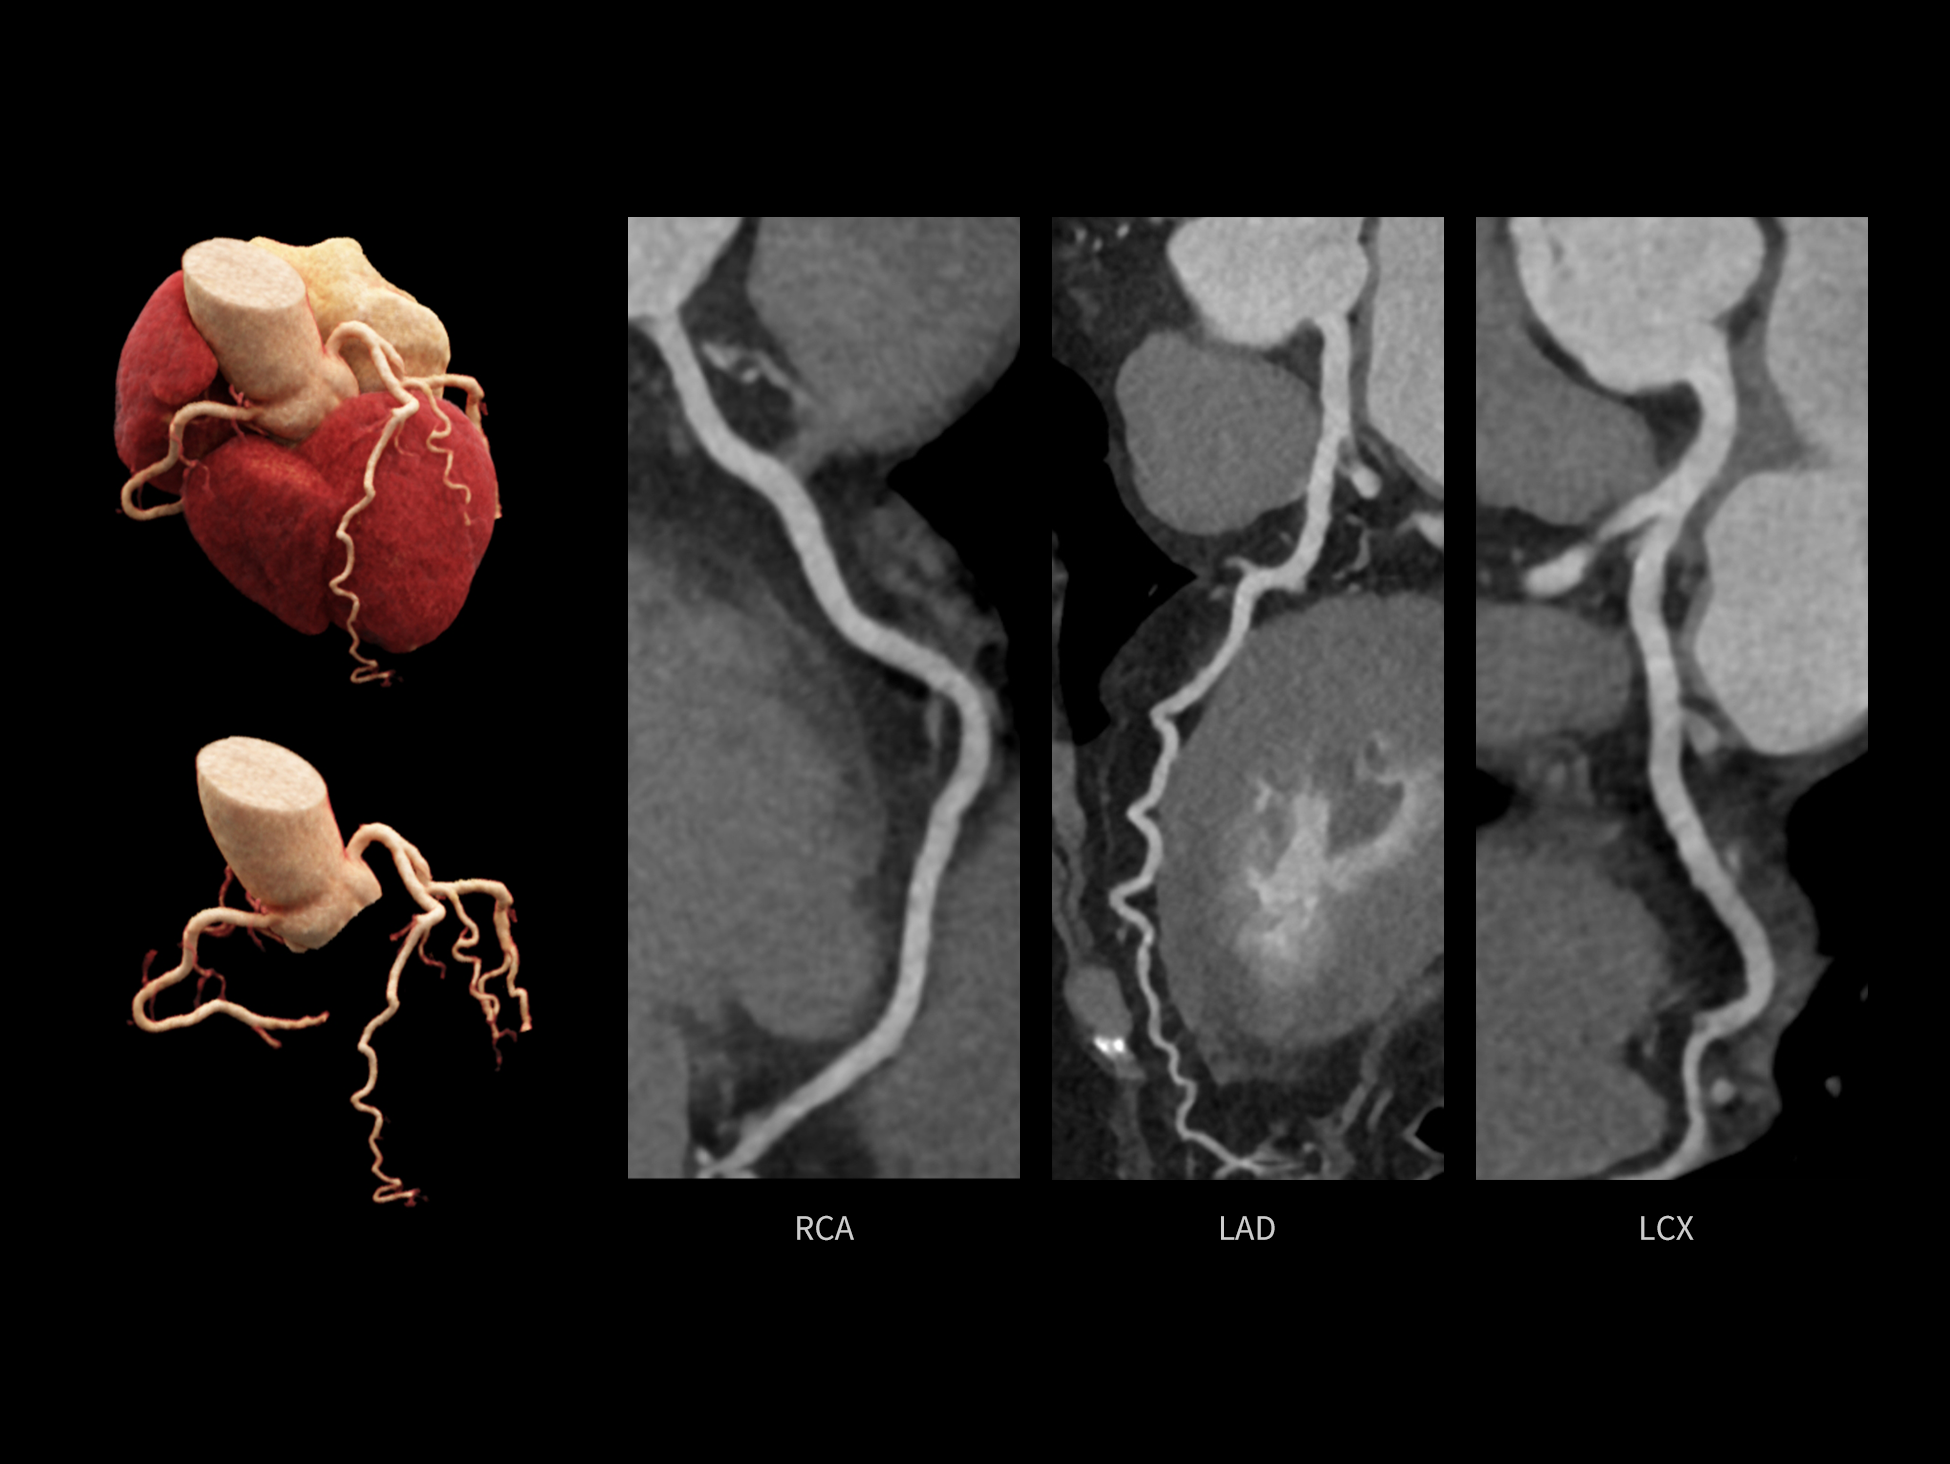

CardioCapture 2.0 通过“识别–追踪–建模–校正”的完整流程,精准分割心脏结构,动态追踪运动轨迹,并构建多时相运动场,最终实现冠脉、瓣膜、心肌及心室结构的同步校正,清晰洞见每一次心跳细微变化,真正将心脏动态掌握于毫秒之间。

CardioCapture 2.0 在目标时相前后重建多时相影像,通过深度学习网络精准提取冠脉中心线,进而建立时相间运动模型,实现对冠脉分段图像的精准运动校正。

CardioCapture 2.0 可对心肌、瓣膜及心室等结构进行同步运动校正。基于深度学习的心脏精细分割,实现了更完整的心脏全局信息提取,能有效抑制全心运动伪影,显著提升心脏细节的清晰度与诊断可靠性。

8ms 全心等效时间分辨率

冠脉运动校正

全心结构运动校正

心脏成像,自由掌控

uCT SiriuX® 以 8ms 全心等效时间分辨率与16cm宽体覆盖,突破传统心脏成像局限,完整呈现搏动中的心脏结构与动态功能;配合无心电门控扫描与智能化工作流,更使心脏检查摆脱心率、配合度与操作复杂度的束缚,实现真正自由从容的成像体验,为临床功能评估提供更深层依据。